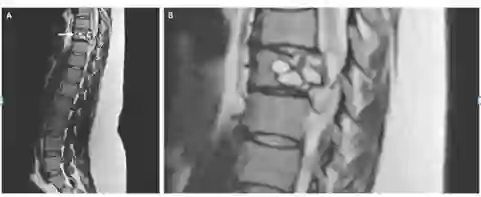

Credit: The New England Journal of Medicine

一名法国妇女称其腿部会出现“电击”的感觉,经检查发现,她患有一种罕见的感染——脊椎里潜伏着绦虫幼虫。

这名女性背部的核磁共振显示,其脊柱有一处病变,需要手术切除。进一步的测试显示,这种病变是由细粒棘球绦虫感染引起的,这是一种小型绦虫,常见于狗和一些农场动物(绵羊、牛、山羊和猪等)。

这种绦虫可引起一种叫做包虫病的疾病,在这种疾病中,幼虫会形成囊肿,并在人体内缓慢生长。这种疾病在法国很少见,研究人员尚不清楚这位妇女是如何感染的。据报道,她曾接触过马和牛等农场动物。研究人员还怀疑,可能是吃了被寄生虫污染的蔬菜导致。在接受了一种抗寄生虫药9个月后,该妇女残留症状消失。

7月11日,《NEJM》杂志发表了该病例的报告。